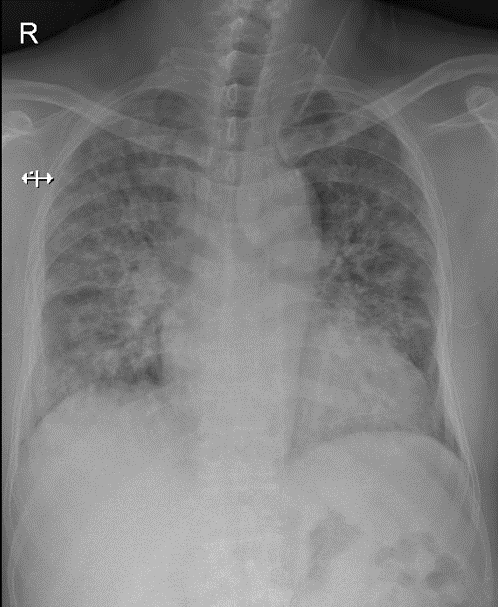

Hãy phân tích tình huống Nam 54 tuổi

1-Thâm nhiểm phế nang lan tỏa hai phổi=> Viêm phổi 2 -Tim (T) lớn